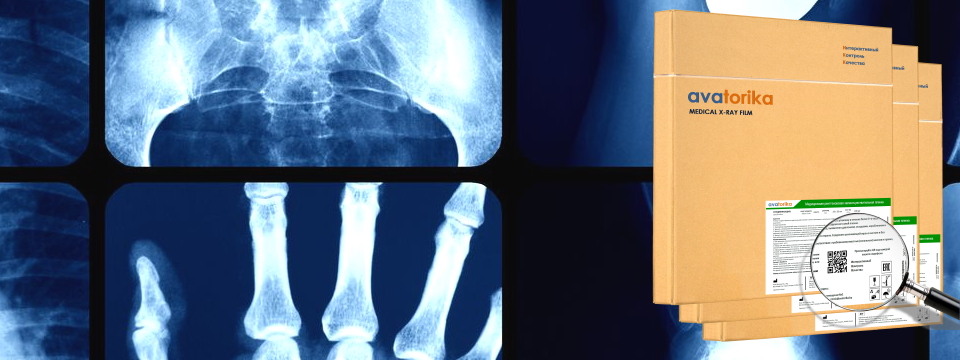

Рентгеновская медицинская пленка "AVATORIKA" - новый стандарт контроля качества рентгенологической диагностики!

Как известно, в последнее время в медицине все чаще стали применяться цифровые рентгеновские системы. Однако, из-за ограниченного разрешения (пикселизации) рентгеновских датчиков качество получаемых цифровых рентгеновских снимков не всегда может отражать всю визуальную полноту изображения, поэтому применение пленочных систем рентгенодиагностики еще весьма востребованно среди рентгенологов. К тому же, себестоимость пленочных рентгеновских снимков существенно ниже себестоимости аналогичных цифровых снимков.

Мы рады представить новый продукт для медицинских учреждений - универсальную медицинскую рентгеневскую пленку "AVATORIKA". Уникальной особенностью изделия является возможность Интерактивного Контроля Качества (ИКК) пленки и получаемых снимков с использованием QR-кода. Пользователю достачно смартфоном сканировать QR-код, нанесенный на этикетку упаковки, чтобы получить полный доступ к информации о пленке и поставщике. ИКК позволяет создать запрос или установить прямой контакт с консультантом - представителем производителя. Благодаря ИКК - качество рентгеновских снимков находится под нашим контролем!

Информацию о стоимости и условиях приобретения рентгеновской пленки можно получить в отделе продаж по тел.: (017) 236-37-36; (029) 376-37-36.

Медицинская рентгеновская пленка AVATORIKA. Высокое качество снимков, Интерактивный Контроль Качества (ИКК), универсальность.